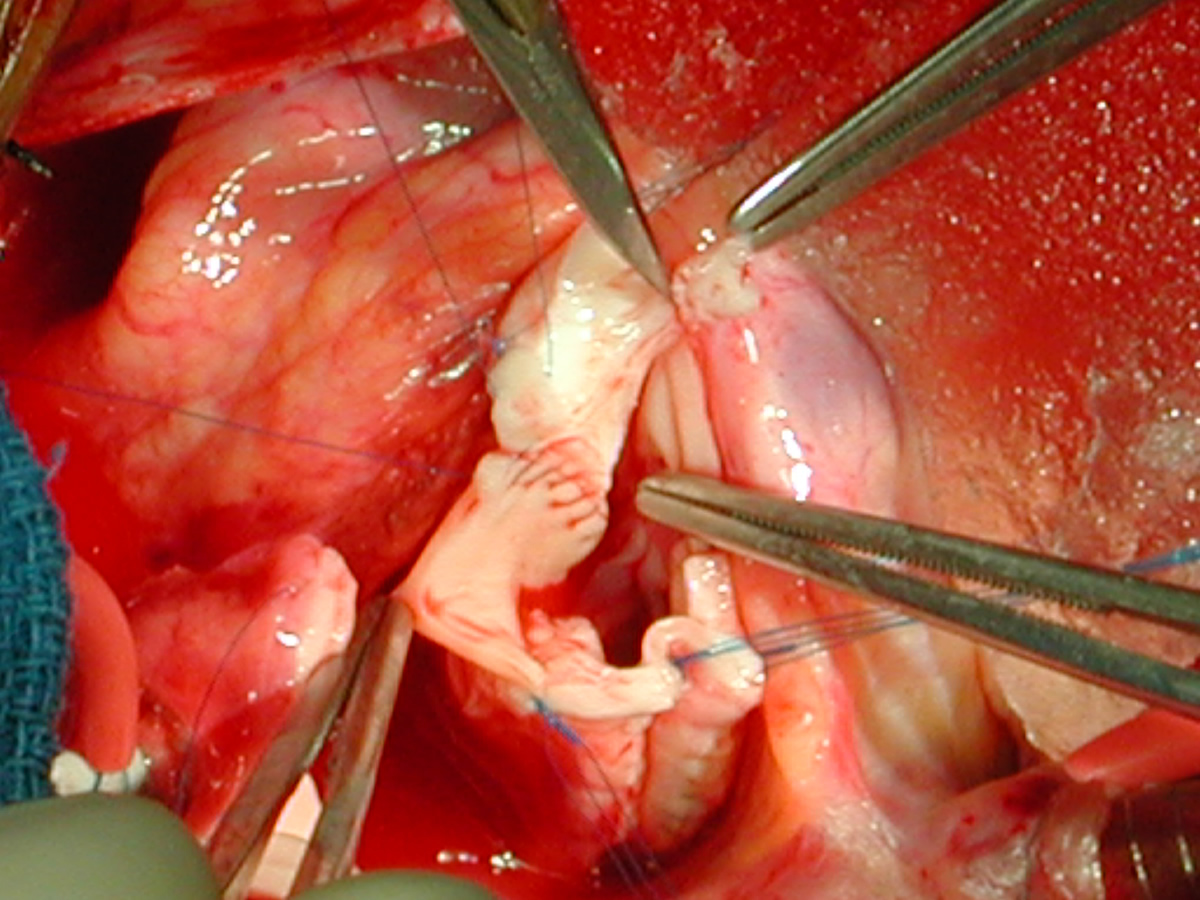

Figures 20 & 21: Third incision has been made to the right of the left coronary orifice. They yellow plastic suture boot on the pickup is pointing out the left coronary orifice. Figures 22 & 23: Proximal ascending aorta now opens widely, revealing the right and left coronary orifices and the normal trileaflet aortic valve below.

Figure Figure Figure Figure